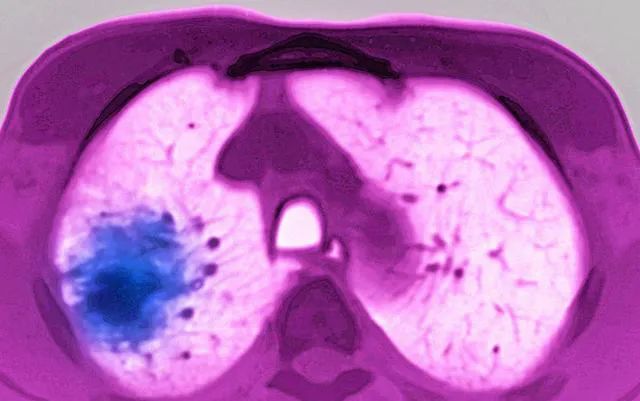

肺占位是個(gè)影像學(xué)概念,是指在胸片或者胸部CT中發(fā)現(xiàn)肺上葉長(zhǎng)了不該長(zhǎng)的東西,也就是說,這個(gè)地方已經(jīng)不是原先的肺組織了,而是被另一種組織給占據(jù)了。這個(gè)不該出現(xiàn)的東西一般為團(tuán)塊影或球形病變,占據(jù)一定的空間,會(huì)使正常肺組織受壓、移位。

對(duì)于典型的肺占位,CT上可以大致判斷是良性還是惡性,是原發(fā)性肺部腫瘤還是轉(zhuǎn)移性腫瘤。比如如果病灶較大,有分葉、毛刺征,以及有周圍浸潤(rùn)性改變,有淋巴結(jié)腫大或者單側(cè)有胸水,則很可能是惡性腫瘤。如果占位性病變發(fā)生在上葉前尖段、下葉背段,周圍有滲出性改變,邊界不清,部分有結(jié)核厚壁空洞,或者存在部分鈣化,則很可能是結(jié)核。有些炎癥性病變CT上也表現(xiàn)為肺占位,比如肺曲霉菌病,經(jīng)過抗真菌治療病灶會(huì)逐漸縮小。臨床上也遇到過肺淋巴瘤、肺滑膜肉瘤、肺癌肉瘤等惡性腫瘤,CT均提示肺部有腫塊,占位性病變。這些疾病必須依靠穿刺病理或術(shù)后病理及免疫組化才能百分百診斷。